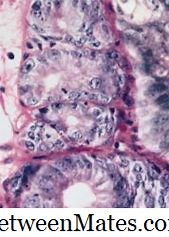

- Goblet Cell